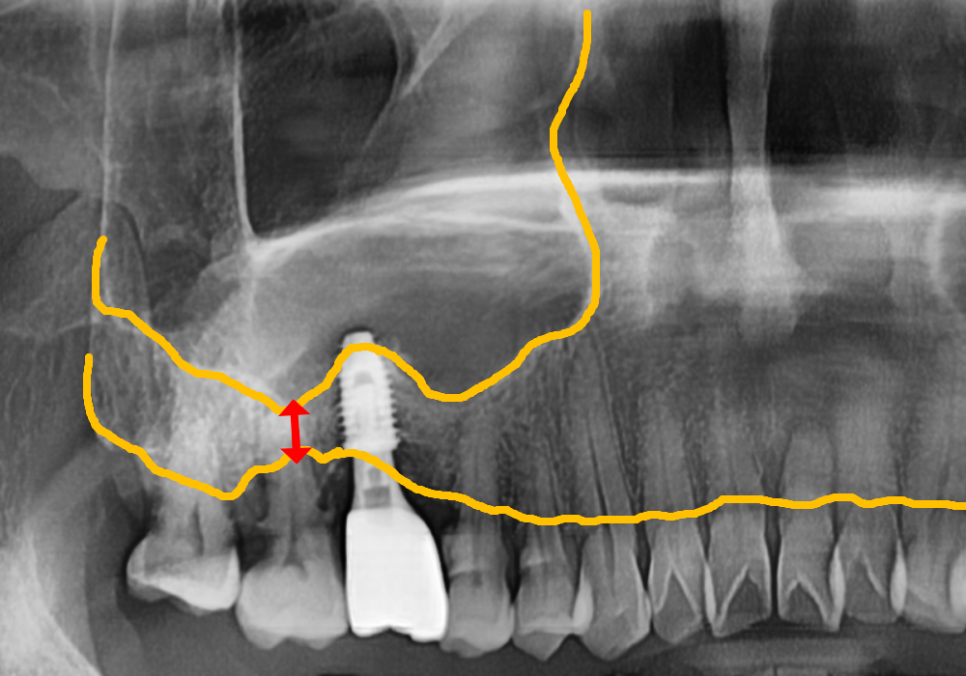

엑스레이를 찍어보니 상황은

생각보다 더 심각했습니다.

251110

보철 내부가 이미 다 삭아서

치아 머리와 뿌리가 툭 끊어져 있는 상태였거든요.

뿐만 아니라, 오른쪽 위 어금니(#18,17) 주변도

염증 때문에 잇몸 뼈가 많이 녹아있는 상태였습니다.

다만 위쪽은 잇몸 뼈가

다소 부족한 상태여서

상악동 거상술이라는 정교한 과정을 통해

뼈를 든든하게 보강한 뒤

임플란트를 심기로 했어요.